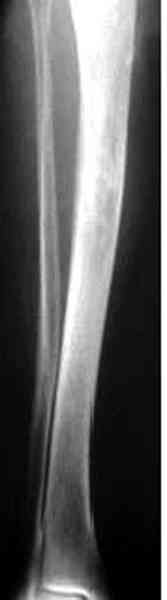

"При его рассмотрении с рентгенологом и морфологом сошлись, что это не фиброзная дисплазия, что было первым предположением по рентгенограммам. В полости было и мягкотканое образование. Окончательно заключение дадут через несколько дней"

По локализации и по характреру опухоли мало напоминает остеобластому, может, представленные биопсийные материалы адамантиномы помогут вашим морфологам дифференцировать опухоль (Basiloid cells, pseudoglandular pattern and peripheral palisading)

В литературе "A Classic Adamantinoma Arising from

Osteofibrous Displasialike Adamantinoma in the Lower Leg: A case report and Review of the Literature похожие снимки.